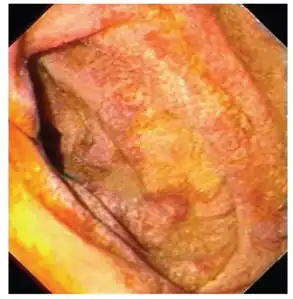

Endoscopy of the duodenum and jejunum can reveal pale yellow shaggy mucosa with erythematous eroded patches in patients with classic intestinal Whipple's disease, and small bowel X-rays may show some thickened folds. Other pathological findings may include enlarged mesenteric lymph nodes, hypercellularity of lamina propria with "foamy macrophages", and a concurrent decreased number of lymphocytes and plasma cells, per high power field view of the biopsy.

Mucosa is swollen and grey-yellowish -